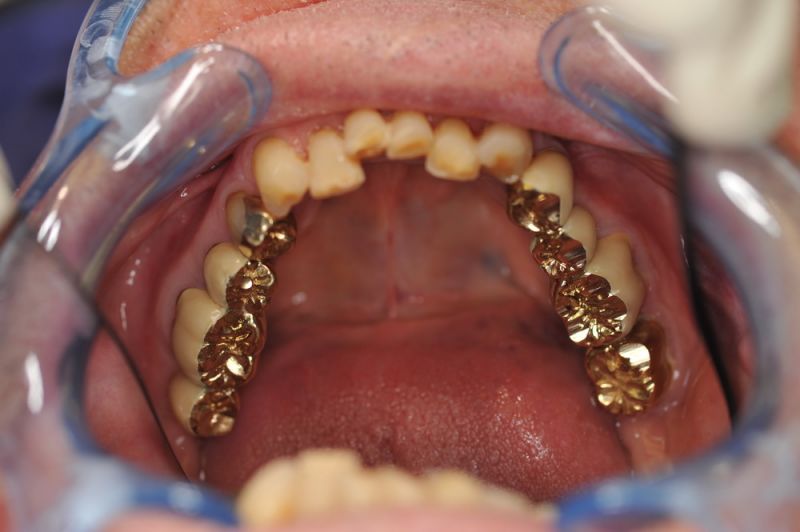

Die funktionstherapeutische Rekonstruktion befindet sich seit 17 Jahren im Munde des Patienten.

Gemeinsam ist man der Auffassung, dass sich heute zum Glück auszahlt, dass man beizeiten die Fundamente im Mund geschaffen hat, von denen der Patient heute im Alter zehrt.